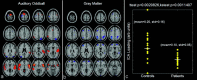

The acquisition of both structural MRI (sMRI) and functional MRI (fMRI) data for a given study is a very common practice. However, these data are typically examined in separate analyses, rather than in a combined model. We propose a novel methodology to perform independent component analysis across image modalities, specifically, gray matter images and fMRI activation images as well as a joint histogram visualization technique. Joint independent component analysis (jICA) is used to decompose a matrix with a given row consisting of an fMRI activation image resulting from auditory oddball target stimuli and an sMRI gray matter segmentation image, collected from the same individual. We analyzed data collected on a group of schizophrenia patients and healthy controls using the jICA approach. Spatially independent joint-components are estimated and resulting components were further analyzed only if they showed a significant difference between patients and controls. The main finding was that group differences in bilateral parietal and frontal as well as posterior temporal regions in gray matter were associated with bilateral temporal regions activated by the auditory oddball target stimuli. A finding of less patient gray matter and less hemodynamic activity for target detection in these bilateral anterior temporal lobe regions was consistent with previous work. An unexpected corollary to this finding was that, in the regions showing the largest group differences, gray matter concentrations were larger in patients vs. controls, suggesting that more gray matter may be related to less functional connectivity in the auditory oddball fMRI task.